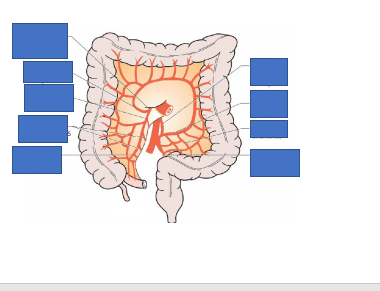

Label this diagram

small bowel obstruction

LOOK at the the valvulae conviventes going all the way through